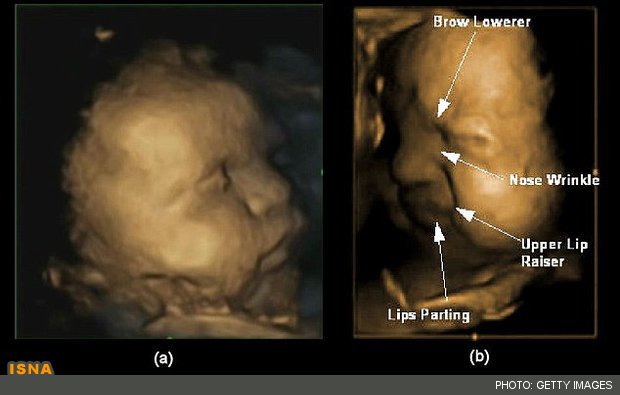

این کودکان همگی به شکلی که ابروهای خود را پائین کشیده، بینیشان چین خورده و دهانشان را میکشند به تصویر درآمدهاند.

محققان این فیلمها را فریم به فریم بررسی کرده و به دنبال بینی چین خورده، ابروی پائین کشیده شده و دیگر حرکات چهره که گویای حالت درد هستند، جستجو کردند.

اسکنهای اولیه در 24 هفتگی به ندرت ترکیب درست این حرکات را نشان میداد اما در 36 هفتگی یا حدود یک ماه مانده به تولد، چینها به تناوب بیشتری یک چهره در حال درد را نشان داده و این حالت در میان دختران و پسران به یک اندازه مشابه بود.